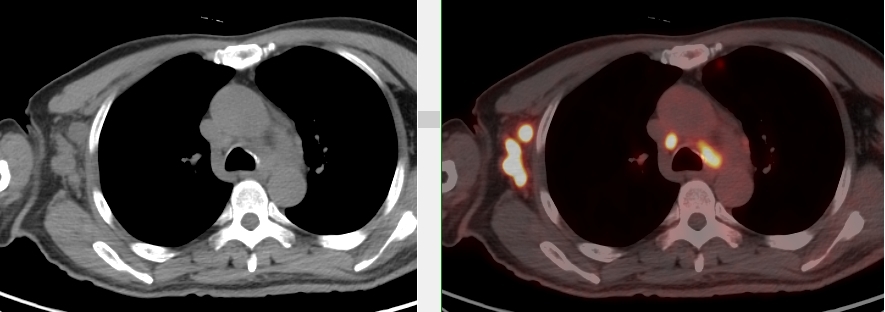

完善PET/CT檢查示:右側(cè)腋窩、雙側(cè)中下頸部、縱隔、雙側(cè)肺門多發(fā)MT,建議淋巴結(jié)活檢。后患者行右腋窩淋巴結(jié)切除活檢術(shù),經(jīng)北京大學(xué)第三醫(yī)院病理科會診示:右腋窩淋巴結(jié)惡性腫瘤,呈淋巴竇內(nèi)生長模式,瘤細(xì)胞呈上皮樣,異型性明顯,伴中性粒細(xì)胞浸潤。結(jié)合病史及免疫組化,考慮為SMARCA4(BRG1)缺失的胸部腫瘤,伴神經(jīng)內(nèi)分泌標(biāo)記表達(dá)。

本例為罕見病理類型的腫瘤,影像學(xué)表現(xiàn)無明顯特異性,診斷困難。強(qiáng)化CT和穿刺病理已基本明確為惡性腫瘤,行PET/CT檢查一是為了全身檢查,完善分期,二是根據(jù)PET代謝情況指導(dǎo)進(jìn)行生物靶區(qū)活檢,進(jìn)一步明確病理診斷。最終,PET/CT除縱隔病變外發(fā)現(xiàn)更多頸胸部淋巴結(jié)代謝異常,綜合考慮后對腋窩淋巴結(jié)進(jìn)行切除活檢,最終得到病理證實(shí)。